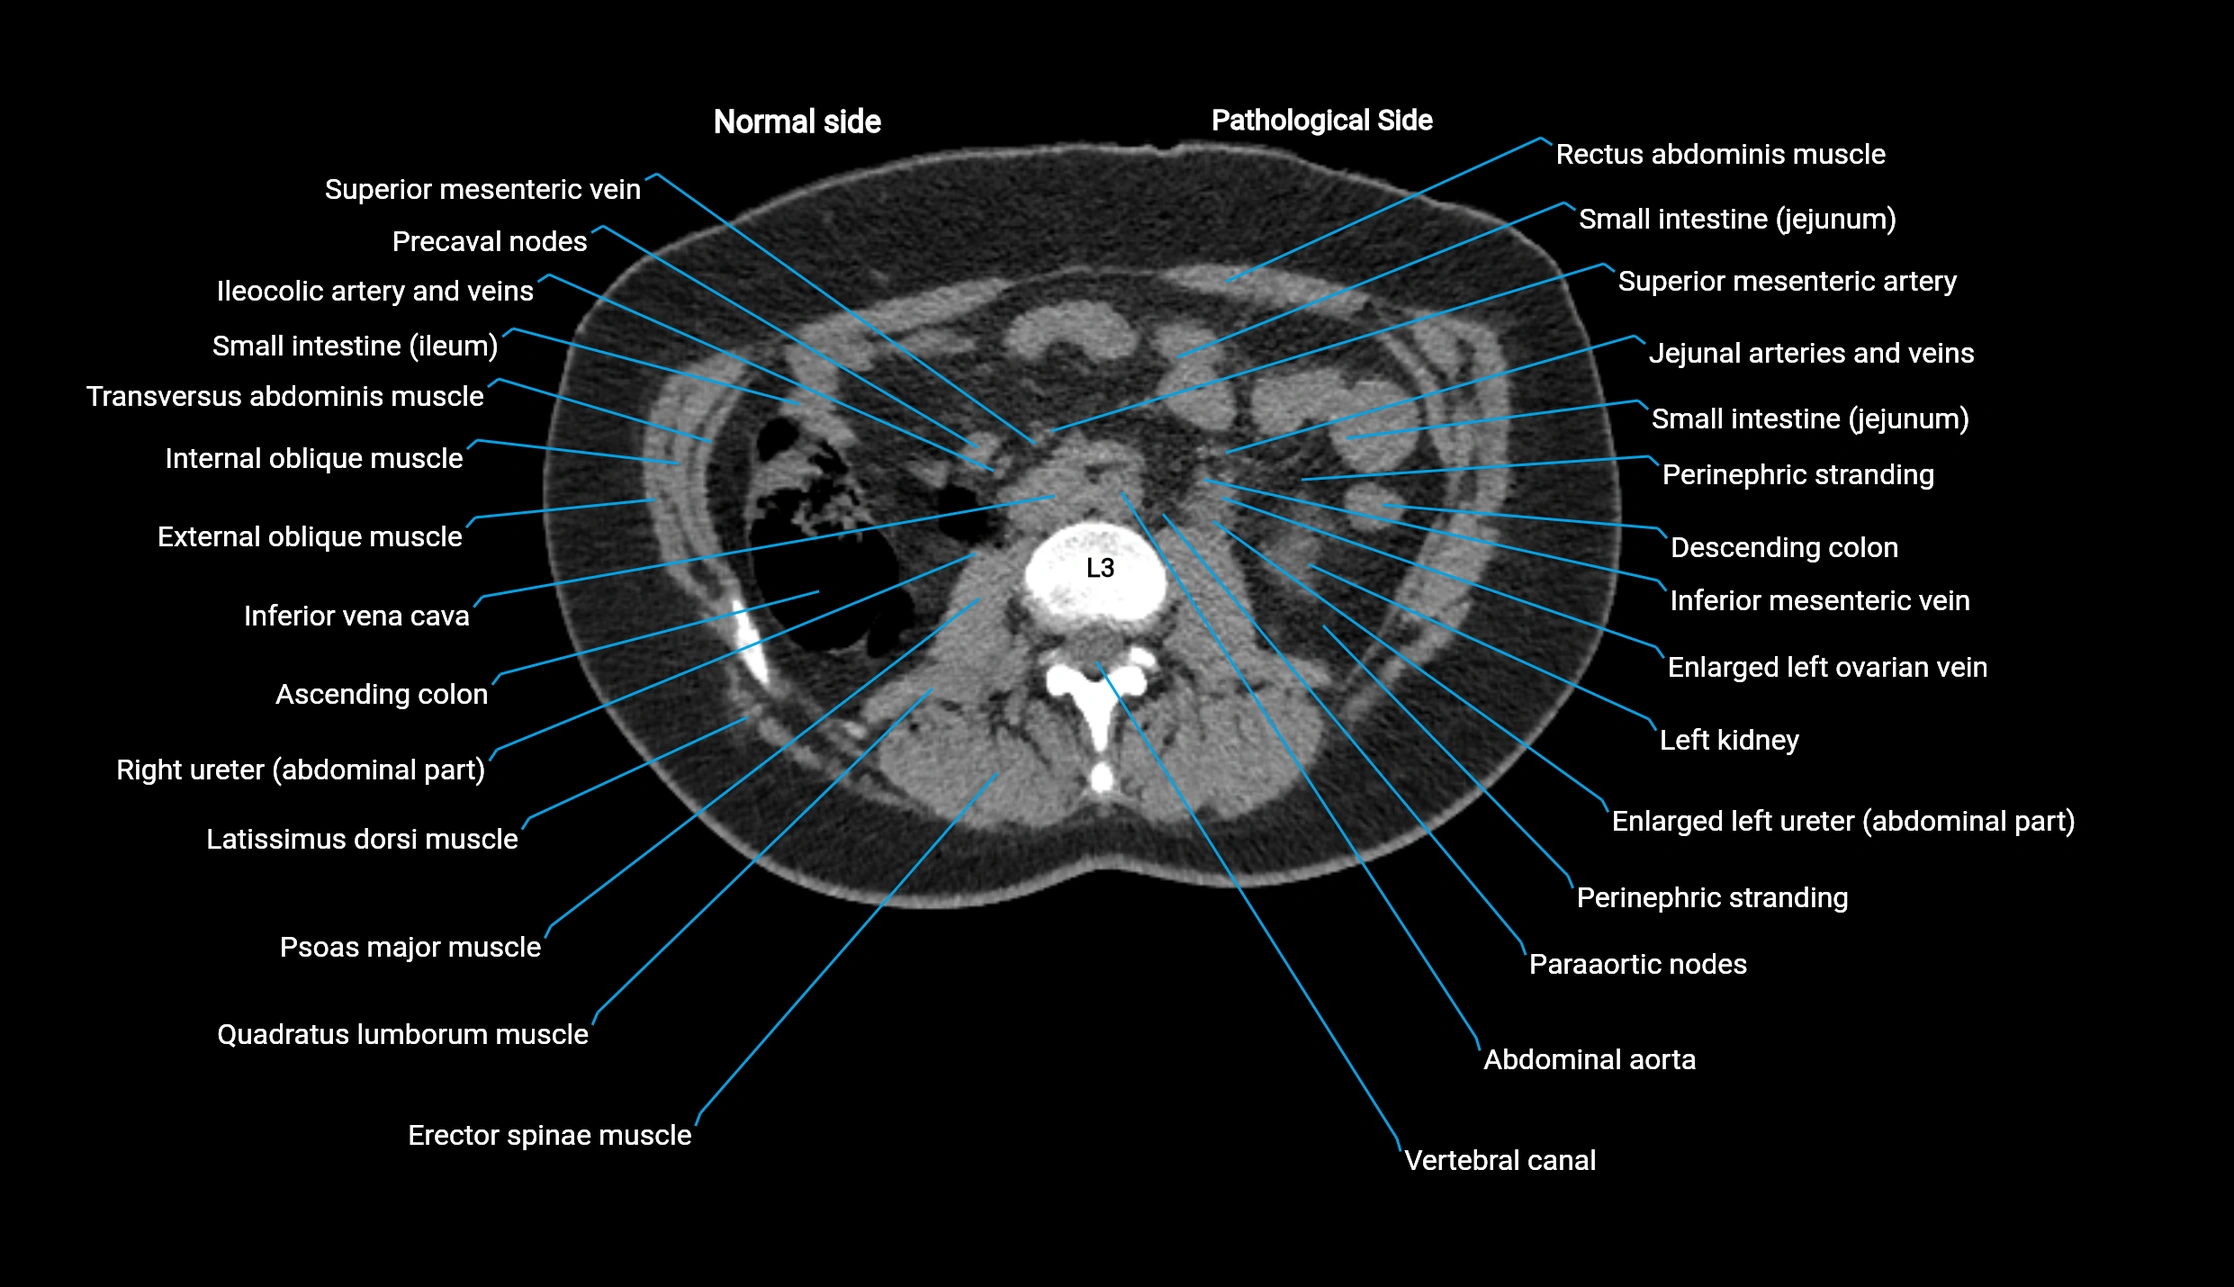

CT Appearance

Non-contrast CT:

• Demonstrates cortical bone of acetabular rim in excellent detail

• Detects fractures, dysplasia, retroversion, or bony overcoverage (pincer impingement)

• 3D reconstructions used in preoperative hip surgery planning